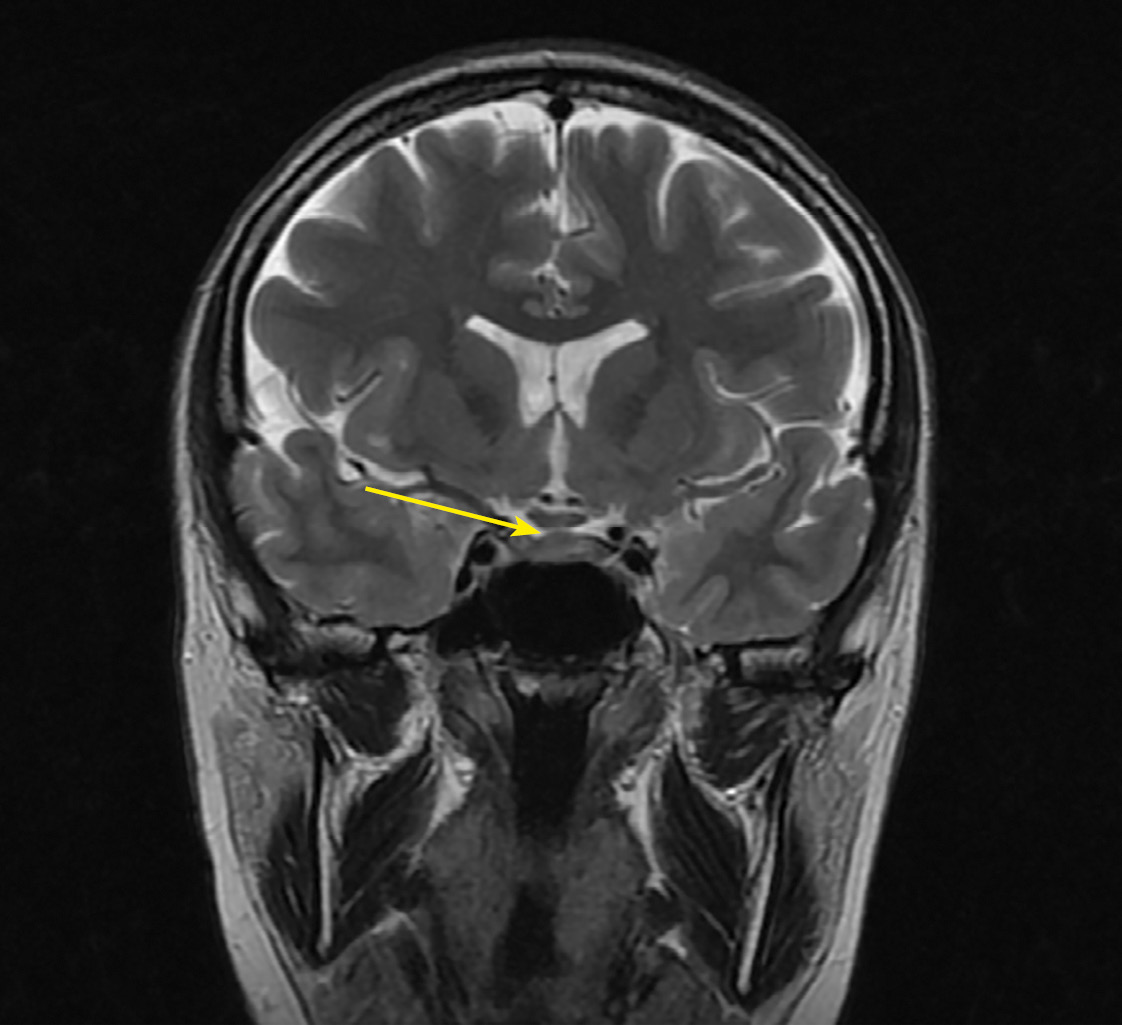

На фоне продолжающейся терапии дексаметазоном, по данным МРТ головного мозга, отмечался регресс изменений хиазмально-селлярной области с утолщением воронки гипофиза, отсутствием сигнала от нейрогипофиза (рис. 3, 4).

Рисунок 3. МРТ головы без контрастного усиления, Т2-взвешенное изображение,

коронарная (фронтальная) проекция. Сохраняется утолщение ножки гипофиза

(изменения указаны стрелкой).